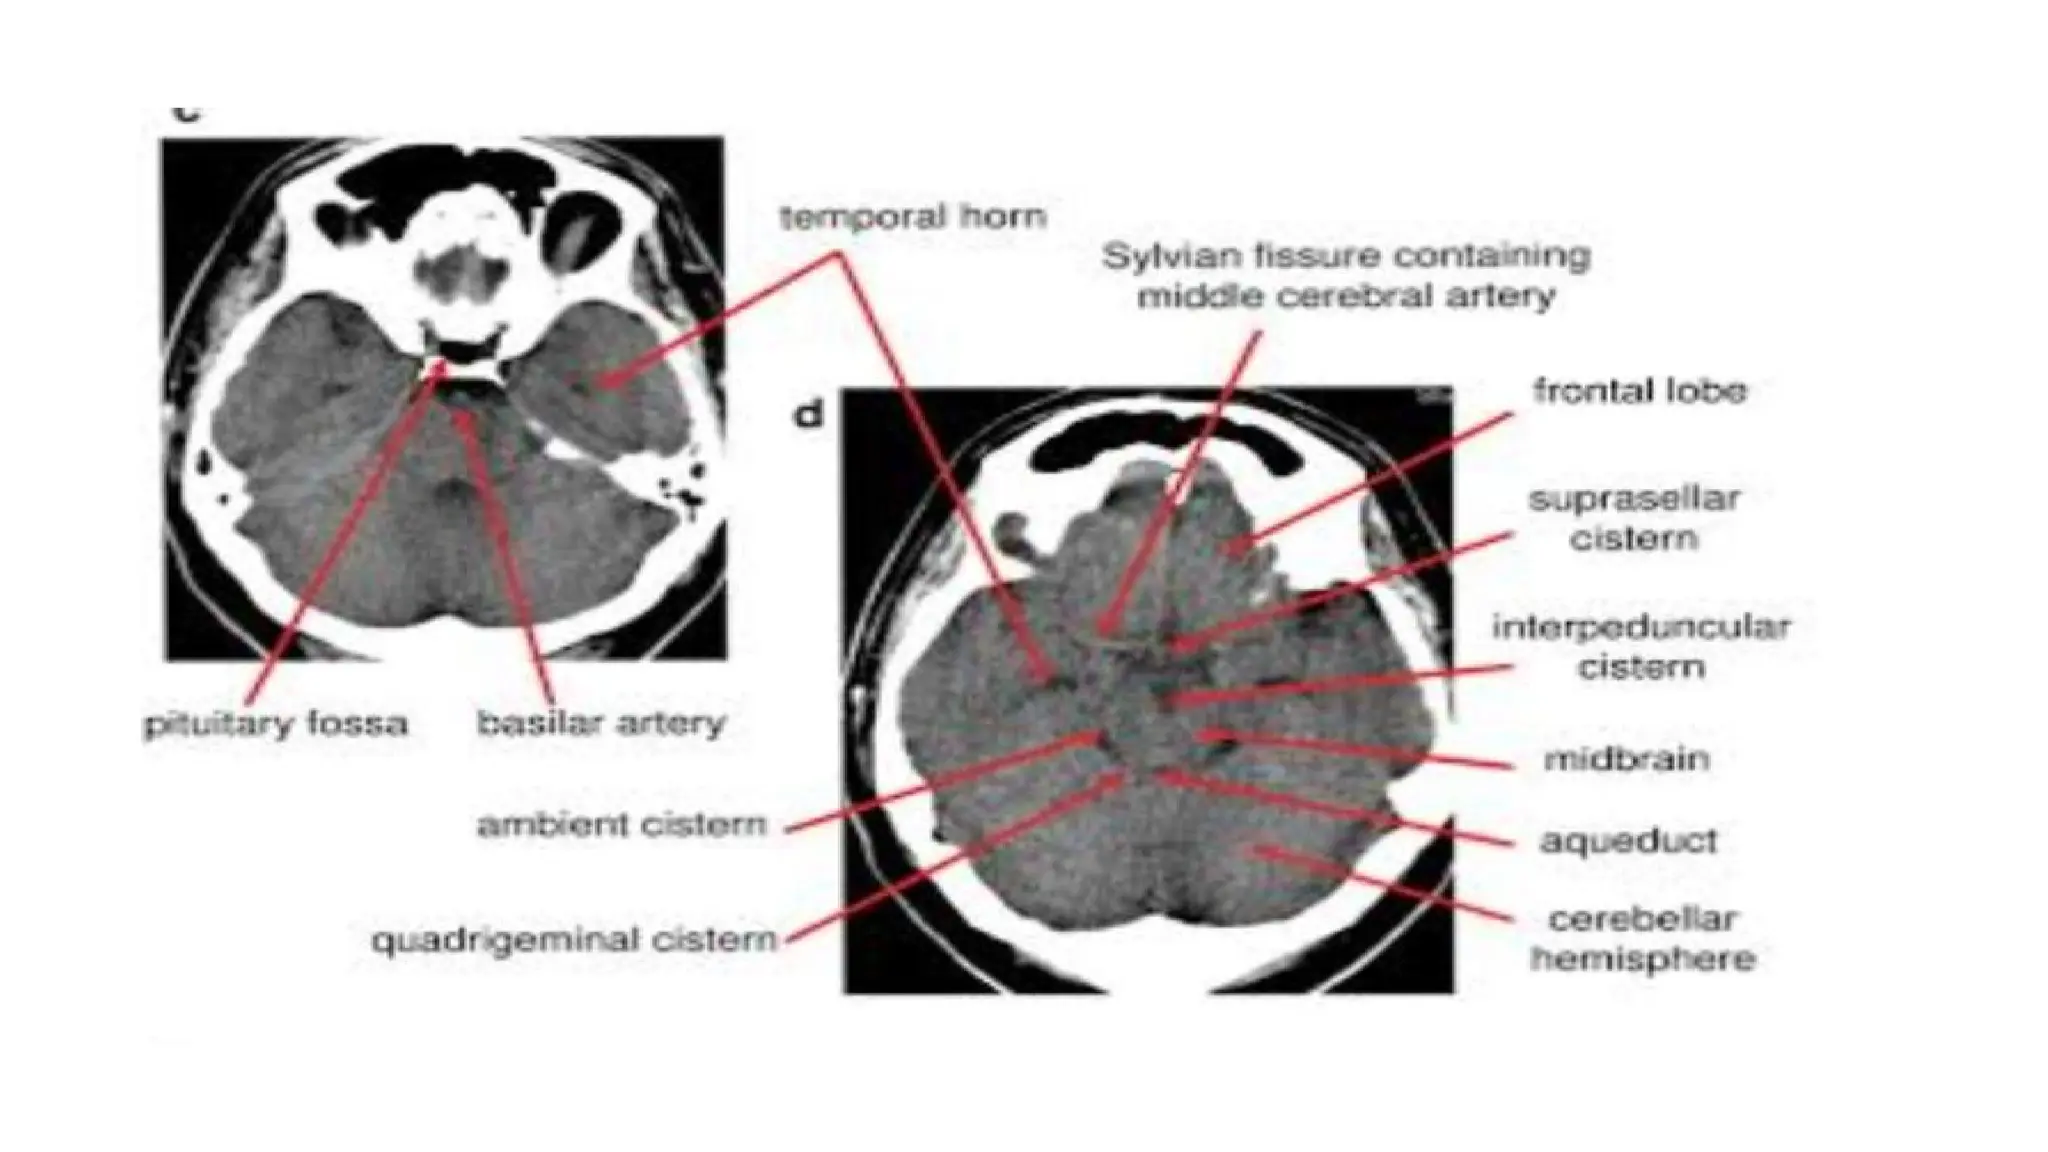

CT SCAN OF BRAIN:

• An imaging technique of the brain that reveal tumors, blood clots,

hemorrhages, or other abnormal anatomy.

• A series of computerized images of the brain at various levels are

taken to reveal normal anatomy or any abnormality.

• Routine scans of the brain usually begin at the base of the skull and

continue superiorly.

• Symmetry - Compare left and right side of the Midline

• Look for midline shift of cranium

• Cross-sectional anatomy - Review anatomical landmark for each

section.

• Brain tissue: gray matter, white matter, intracerebral lesions

• CSF space : ventricle (dilated or not)

• Skull and soft tissue: scalp swelling, fractures, sinuses, orbit

• Subdural windows: Look for blood collection adjacent to the skull

• Bone windows: Skull, orbit and sinuses, intracranial air